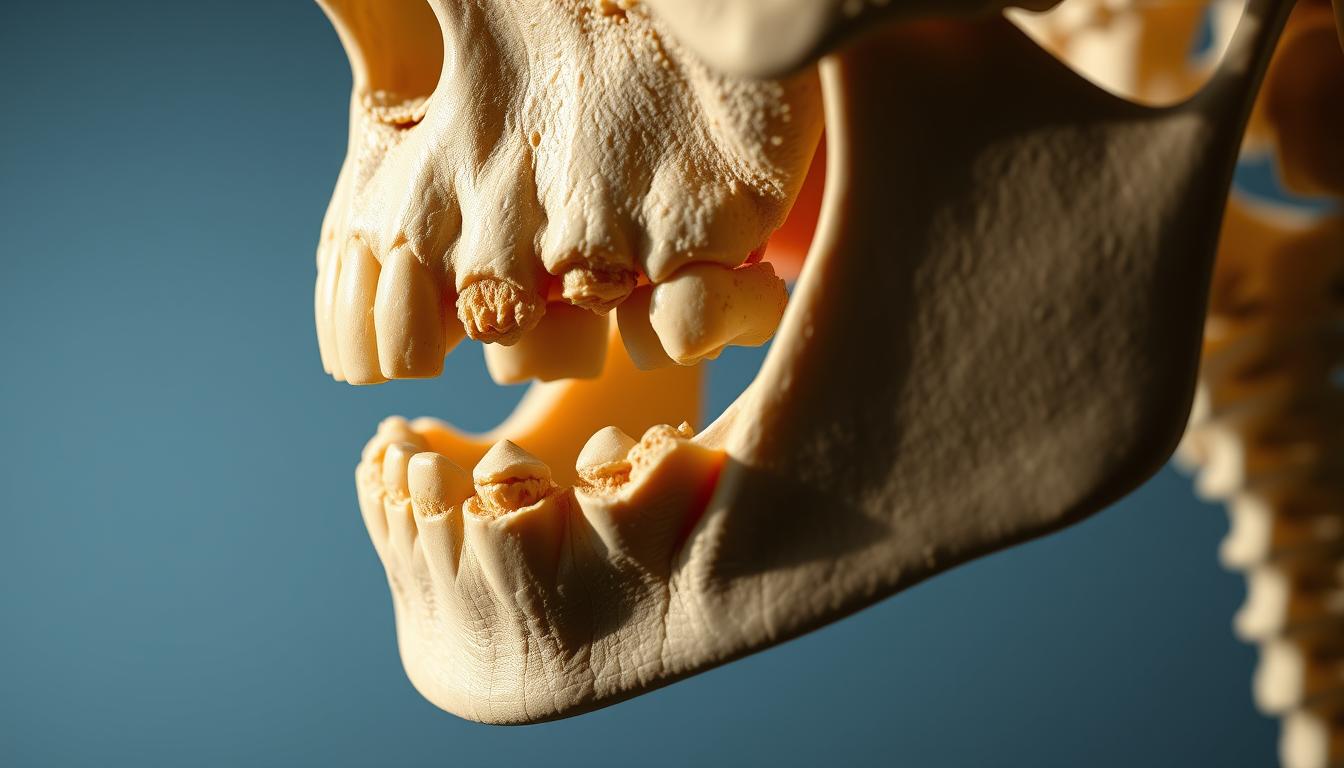

Osteonecrosis of the Jaw (ONJ) is a serious condition. It causes bone death in the jaw. This can lead to a lot of discomfort and other problems.

Images show how ONJ gets worse over time. They are key for doctors to diagnose and see how bad it is.

Doctors look at these images to figure out how far ONJ has spread. They then plan the best treatment. This article will cover ONJ’s causes, symptoms, and how to treat it.

As ONJ gets worse, symptoms become more severe and disabling. Advanced symptoms include severe pain, significant bone exposure, and infection. This can lead to osteomyelitis or other serious issues.

Early-stage ONJ shows small bone changes that might not be easy to see on X-rays. These changes can include osteochondral necrosis, where both bone and cartilage die. The affected area might look denser or show a slight loss of bone structure.

Visual Characteristics of ONJ Across Different Stages

It’s important to know how ONJ looks at each stage to treat it well. ONJ changes a lot as it progresses, showing different signs at each stage.

Stage 1: Exposed Bone Without Infection

Stage 1 shows exposed bone but no infection. This is a key time to act fast to stop things from getting worse.

Stage 2: Exposed Bone With Infection

Stage 2 has exposed bone and signs of infection like pain or swelling. Osteonecrosis treatment here means fighting the infection and fixing the bone.

Stage 3: Advanced Lesions and Complications

Stage 3 has serious bone damage, maybe with fractures or fistulas. Treating Osteonecrosis here needs a big plan, possibly surgery.